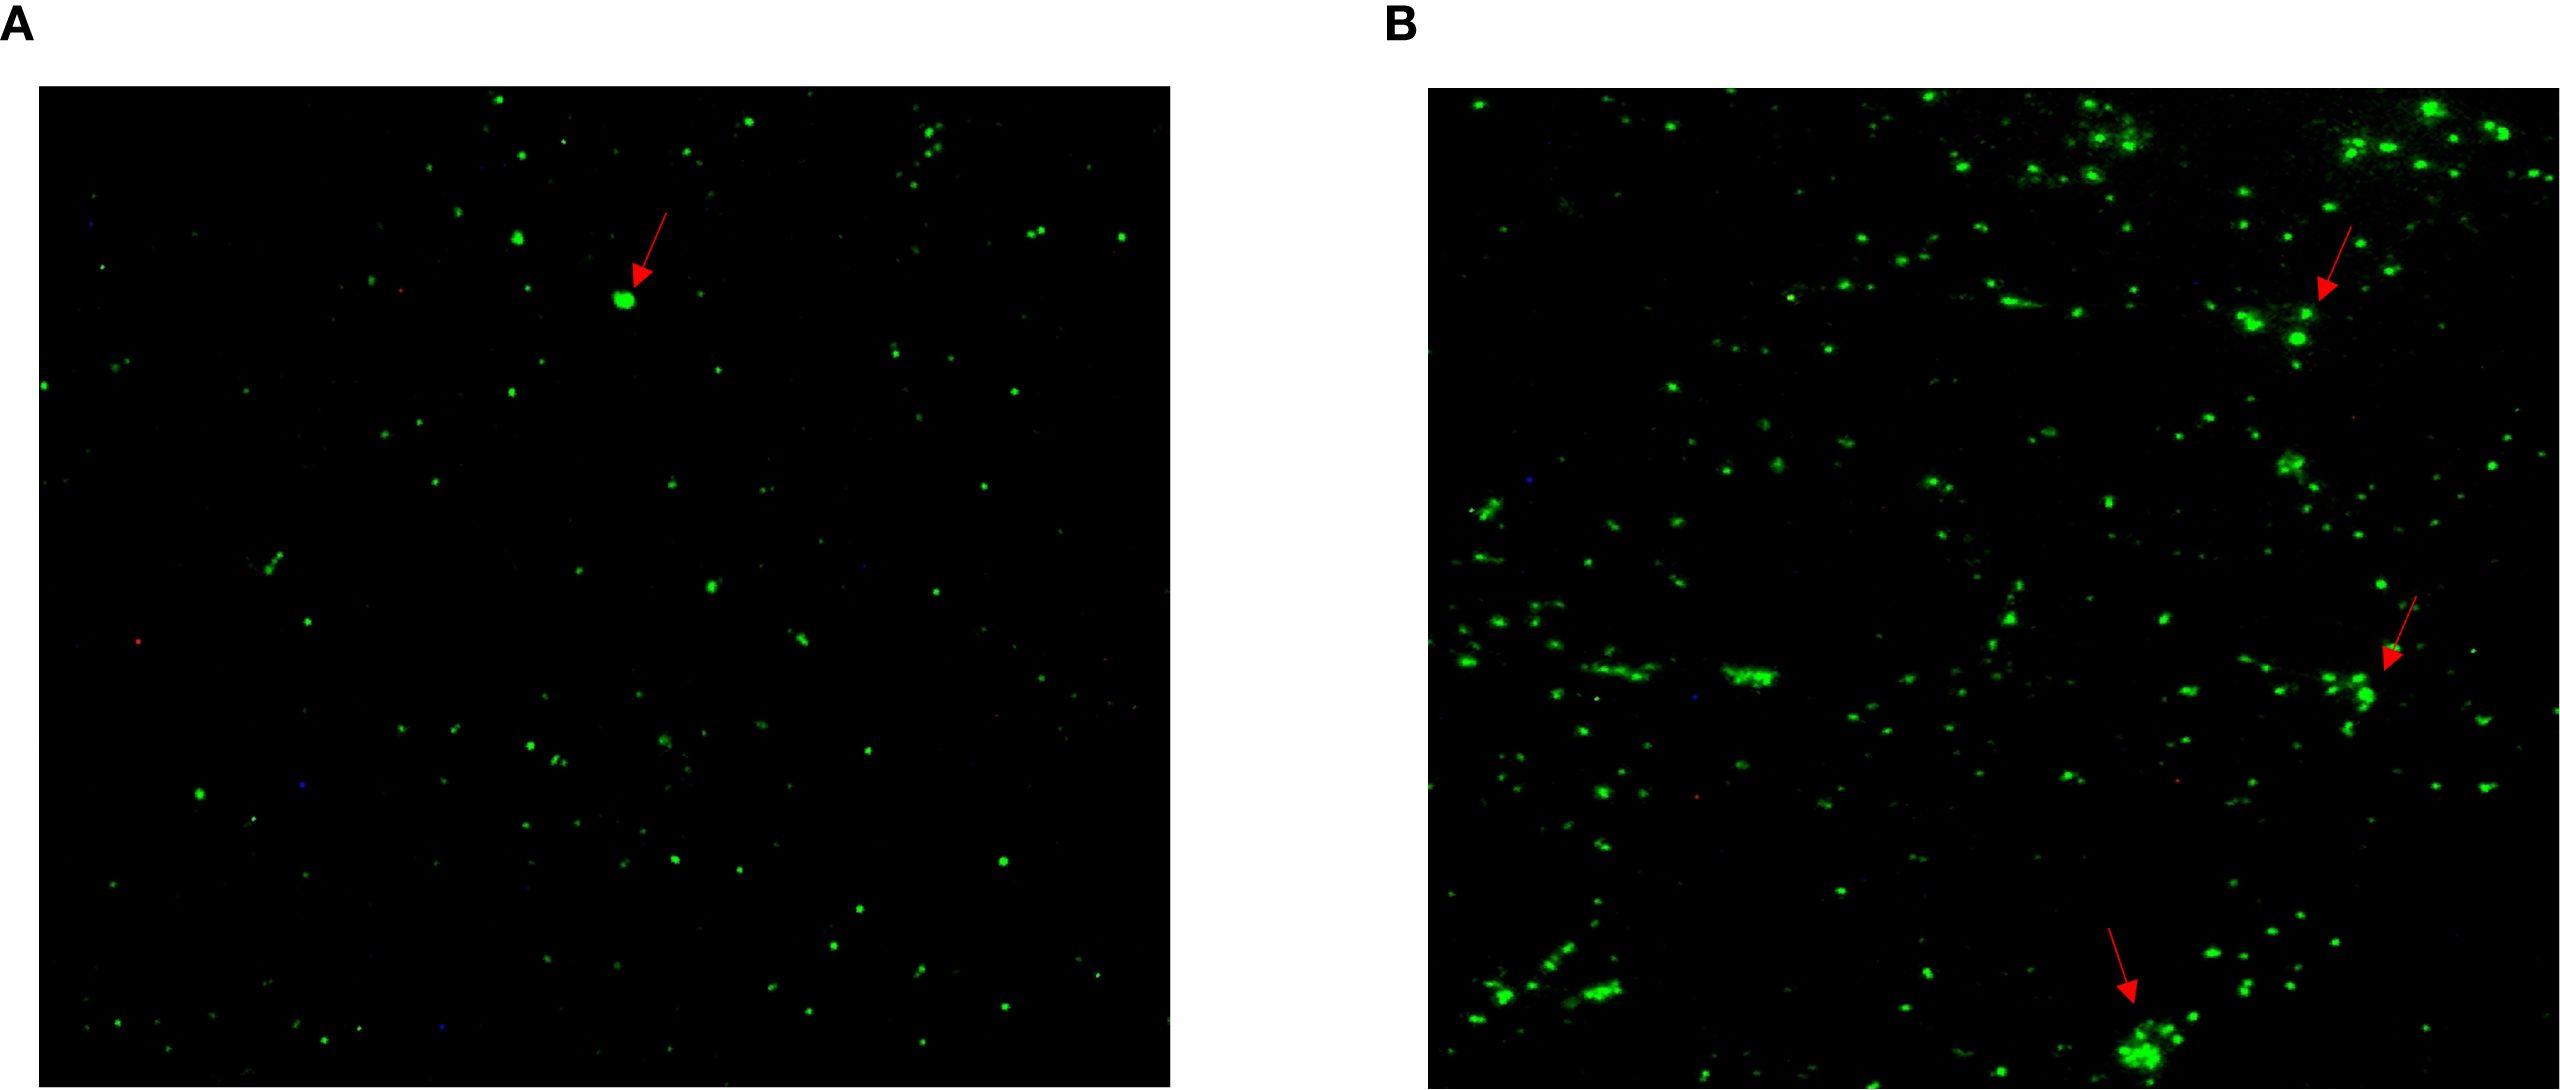

After the patient’s hospital admission, his chest X-ray revealed bilateral pneumonia and ground-glass opacity, and he was prescribed oxygen therapy and doxycycline. Afterward, lesions with ground-glass opacity were reduced, but pulmonary consolidation was still observed in the lungs (Supplementary Figure S2). Based on 23S rDNA amplification, a positive 172-bp band of C. psittaci was detected in the patient’s alveolar wash, while his tracheal mucosa and throat swabs were negative (Figure 1A). Other family members, the nurses, the attending physician, and the house chickens were negative for C. psittaci (Figure 1B). Afterward, qPCR results showed that the patient’s alveolar wash was positive for C. psittaci. Subsequently, positive C. psittaci was identified in the patient’s alveolar wash and throat swab, and his sons’ throat swab. However, a negative reaction was found in his tracheal mucosa and other close contacts’ samples (Figure 2). The ompA gene sequence of the C. psittaci strain was determined and submitted to GenBank (accession number: OR616243). After inoculation into SPF embryonated eggs, typical intracellular inclusions were observed using immunofluorescence staining (Figure 3).

Figure 3. Positive Chlamydia psittaci strain was isolated from patient’s throat swab samples using immunofluorescence staining. Blue, 4',6-diamidino-2-phenylindole (DAPI)-stained host cells. Green, fluorescein isothiocyanate (FITC)-labeled lipopolysaccharide (LPS) antibody against Chlamydia.

Figure 4. Specific antibodies against Chlamydia psittaci during patient’s hospital admission. (A) Positive antibody to C. psittaci was observed on December 25, 2019. (B) Highly intensive C. psittaci-specific antibodies were observed in a time-course manner on December 27, 2019.